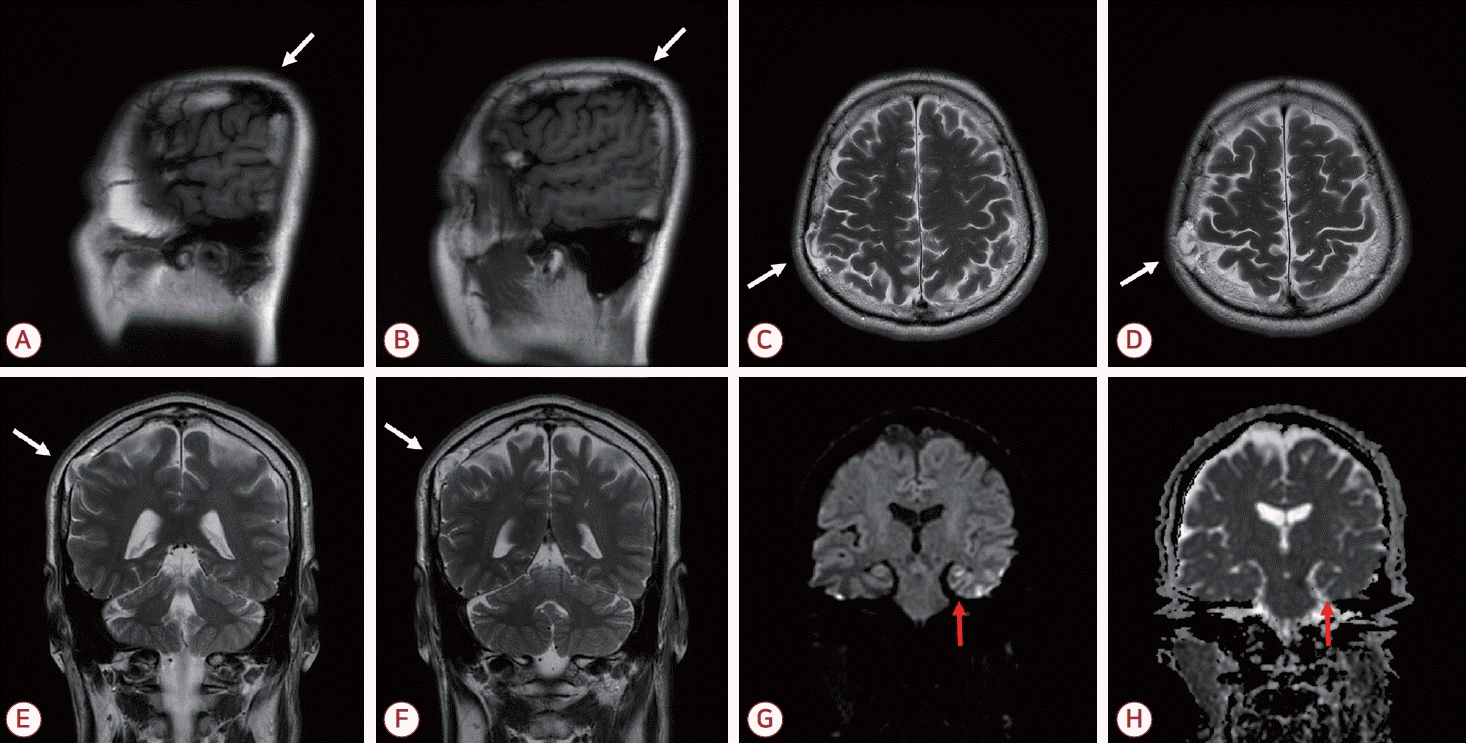

61세 남자가 일주일 전 발생한 5시간 동안의 기억상실로 내원하였다. 동반 증상 및 두부 외상 병력은 없었고 신경계 진찰, 간이정신상태 검사, 뇌파 검사에서 이상은 없었다. 뇌자기공명영상에서 정상 뇌와 등신호를 보이고 우측 두정엽과 연속성을 갖는 조직이 뇌척수액 영역과 함께 두개판내(intradiploic) 공간에 위치해 있었으며 우측 두정골의 결손이 관찰되었다. 확산강조영상에서는 좌측 해마에 점상 고신호강도 병변이 확인되었다(Fig.).

Sagittal T1-weighted image (A, B), axial T2-weighted images (C, D), coronal T2-weighted images (E, F), DWI (G), and ADC image (H) from the brain MRI. (A-F) Parenchymal tissue showing signal intensity identical to normal brain and continuous with the right parietal lobe is seen within the intradiploic space along with cerebrospinal fluid, accompanied by a defect of the right parietal bone (white arrow). (G, H) A punctate hyperintense lesion with mild ADC reduction is noted in the left hippocampus on DWI (red arrow). DWI; diffusion weighted image, ADC; apparent diffusion coefficient, MRI; magnetic resonance imaging.